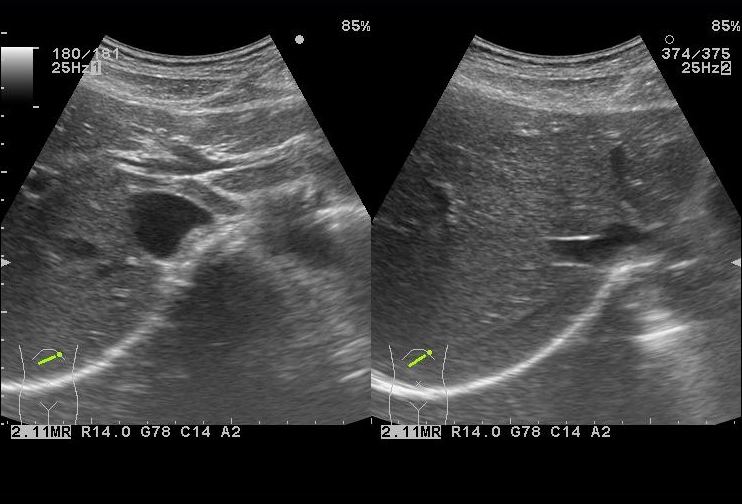

楽天ブックス: 日超検 腹部超音波テキスト第3版 - 日本超音波, 腹部エコー】画像一覧 | 症例・事例 | 矢野医院|射水市の内科,

腹部エコー】画像一覧 | 症例・事例 | 矢野医院|射水市の内科, 腹部超音波検査(腹部US検査、腹部エコー検査)、 血管・体表超,

腹部超音波検査(腹部US検査、腹部エコー検査)、 血管・体表超, 腹部超音波による検査|公益財団法人東京都予防医学協会「元気で腹部超音波テキスト 改訂第三版初心者の方でも分かりやすく書かれています。自宅保管の為、カバーに細かな傷などはありますが、中身は綺麗です。ページの切り取り、破れ、マーカーや書き込みなどはありません。状態は良いと思います。

腹部超音波による検査|公益財団法人東京都予防医学協会「元気で腹部超音波テキスト 改訂第三版初心者の方でも分かりやすく書かれています。自宅保管の為、カバーに細かな傷などはありますが、中身は綺麗です。ページの切り取り、破れ、マーカーや書き込みなどはありません。状態は良いと思います。